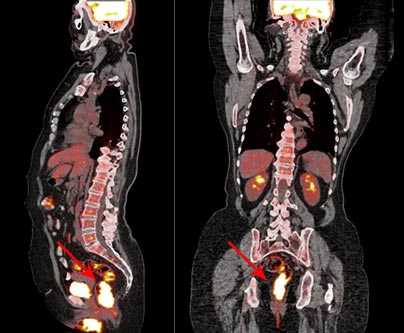

ПЭТ/КТ всего тела

ПЭТ/КТ (PET/CT) — эффективный и современный метод диагностики онкологических заболеваний. Метод сочетает возможности позитронно-эмиссионной (ПЭТ) и компьютерной (КТ) томографий и позволяет с высокой долей уверенности установить наличие злокачественного образования.

Для выявления патологических клеток применяются различные радиофармпрепараты. ПЭТ/КТ всего тела проводится с введением 18F-фтордезоксиглюкозы (18F-ФДГ) - это препарат, который готовится накануне исследования, с учетом индивидуальных особенностей пациента. Диагностика основана на оценке скорости обмена веществ клеток на молекулярном уровне, поэтому позволяет выявить злокачественную опухоль размером от 4-5 мм. Опухоли меньших размеров не позволяют выявить разрешающие способности современных ПЭТ/КТ-сканеров.

ПЭТ/КТ способна диагностировать те опухолевые очаги, которые невозможно выявить с помощью других средств визуализации - УЗИ, рентгена, КТ, МРТ.

На полученном при сканировании тела пациента изображении клетки опухоли видны как яркие пятна, так как они поглощают больше 18F-ФДГ, чем здоровые ткани. Врач имеет возможность сделать выводы о злокачественности образования, размерах и стадии процесса по насыщенности цвета, размеру, локализации и количеству «горячих очагов».